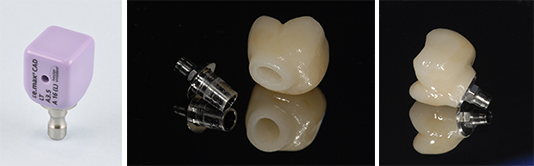

Qu’il s’agisse d’un pilier de cicatrisation anatomique, d’une couronne provisoire ou d’une couronne d’usage, le principe de réalisation est le même. Il repose sur l’utilisation de blocs de matériau pré-percés (céramique ou PMMA) et d’embases en titane (TiBase) permettant la confection d’éléments trans-vissés (Fig. 12 a, b et c).

Fig. 12 : Les constituants d’une couronne trans-vissée

12a : Le bloc de céramique pré-percé

12b : L’embase titane et la supra-structure cosmétique maquillée

12c : La couronne prête à être mise en place